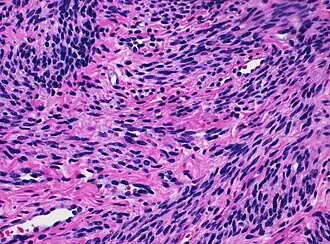

![]() Histology of myometrium | |

The myometrium is the middle layer of the uterine wall, consisting mainly of uterine smooth muscle cells (also called uterine myocytes[1]) but also of supporting stromal and vascular tissue.[2] Its main function is to induce uterine contractions.

The molecular structure of the smooth muscle of myometrium is very similar to that of smooth muscle in other sites of the body, with myosin and actin being the predominant proteins.[1] In uterine smooth muscle, there is approximately 6-fold more actin than myosin.[1] A shift in the myosin expression of the uterine smooth muscle may be responsible for changes in the directions of uterine contractions during the menstrual cycle.[1]